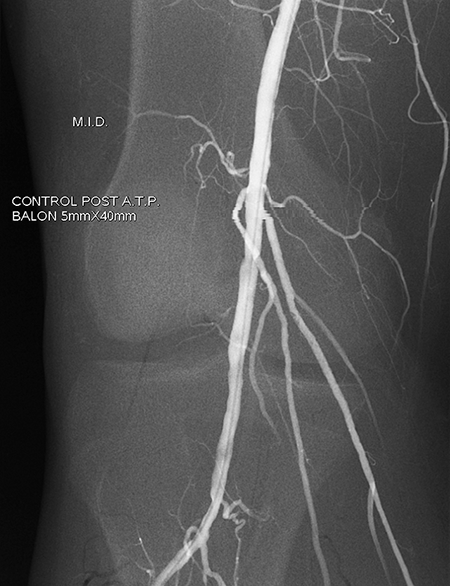

En algunos casos para identificar grado de afectación se debe realizar arteriografía u otras pruebas de imagen.

Cuando la enfermedad arterial periférica esta instaurada, hay que hacer un estudio minucioso para determinar si el tratamiento debe ser conservador o si es necesario realizar tratamientos endovasculares para hacer llegar mas sangre a las piernas.

ANTES

DESPUÉS